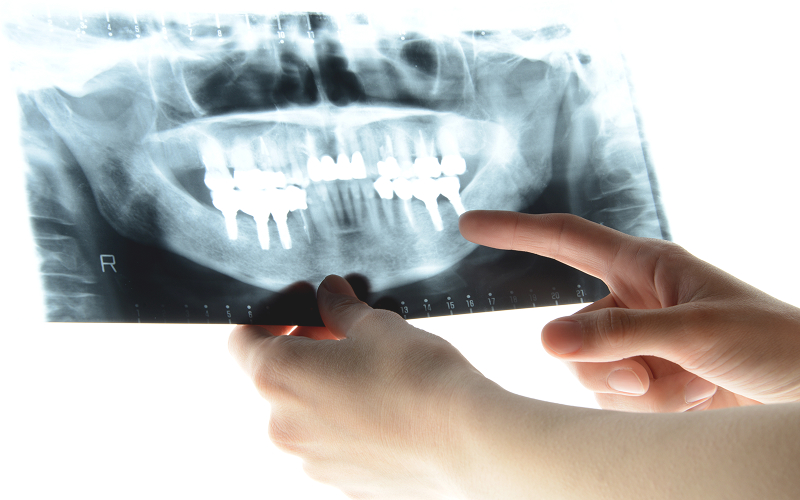

当院では、最新のCT設備を導入し、わずか3秒で高精度な撮影を実現します。放射線量を抑えた安全な診断が可能なため、患者様の身体への負担を最小限に抑えられます。また、目立ちにくいホワイトワイヤーもご用意しており、矯正中の見た目を気にされる方にも安心して治療を受けていただけます。さらに、他の患者様との接触を最小限に抑えた診療環境を整えることで、プライバシーにも配慮しています。丁寧なカウンセリングにより、患者様一人ひとりの状態や生活スタイルに合わせた治療計画をご提案いたします。